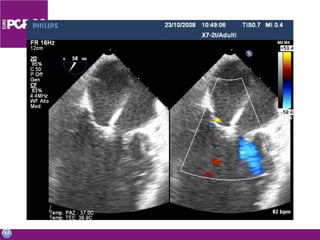

Imaging and other enabling technologies ICE 3D echo Multislice CT MRI Stereotaxis Combinations

Transeptal puncture “The” endovascular skill for mitral valve Difficult and risky Echo guidance Safety Precision A surgeon invented it – so we can learn it Few (<5%) interventional cardiology centers routinely perform this technique

Imaging and otherenabling technologies ICE 3D echo Multislice CT MRI Stereotaxis Combinations

• #53 Not only transeptal puncture can be facilitated by echo, but generally speaking….. Imaging is the most important enanbling technoilogy for PVI and surgeons involved in the field should be exposed to most of these technolgies